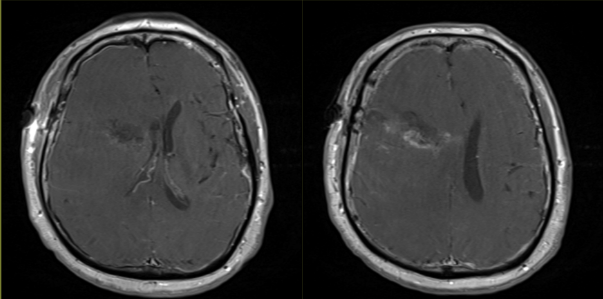

寻找辨认作为计划进入点的脑沟并导航确认。打开该处蛛网膜,13.5mm*60mm的BrainPath工作套件和导航探针连接匹配,随后将其沿计划路径穿刺进入肿瘤内部。套件外鞘借助Greenberg钳和Shepherd钩固定于Mayfield头架上。

显微镜下识别肿瘤,肿瘤切除看到白质后便是肿瘤的内侧界。逐步回退工作套管让肿瘤自动被挤入手术视野。吸引器、显微垂体抓钳和Myriad设备交替配合切除肿瘤直至镜下可见一层白质。保存肿瘤标本并取样送病理检查。

镜下和导航下确认肿瘤切除满意后术腔彻底止血,硬膜原位缝合。

术后患者安返神经ICU。 术后使用地塞米松并于1周内迅速减量撤药。 使用左乙拉西坦500mg bid预防性抗癫痫。 术后第1天复查MRI见肿瘤近全切。